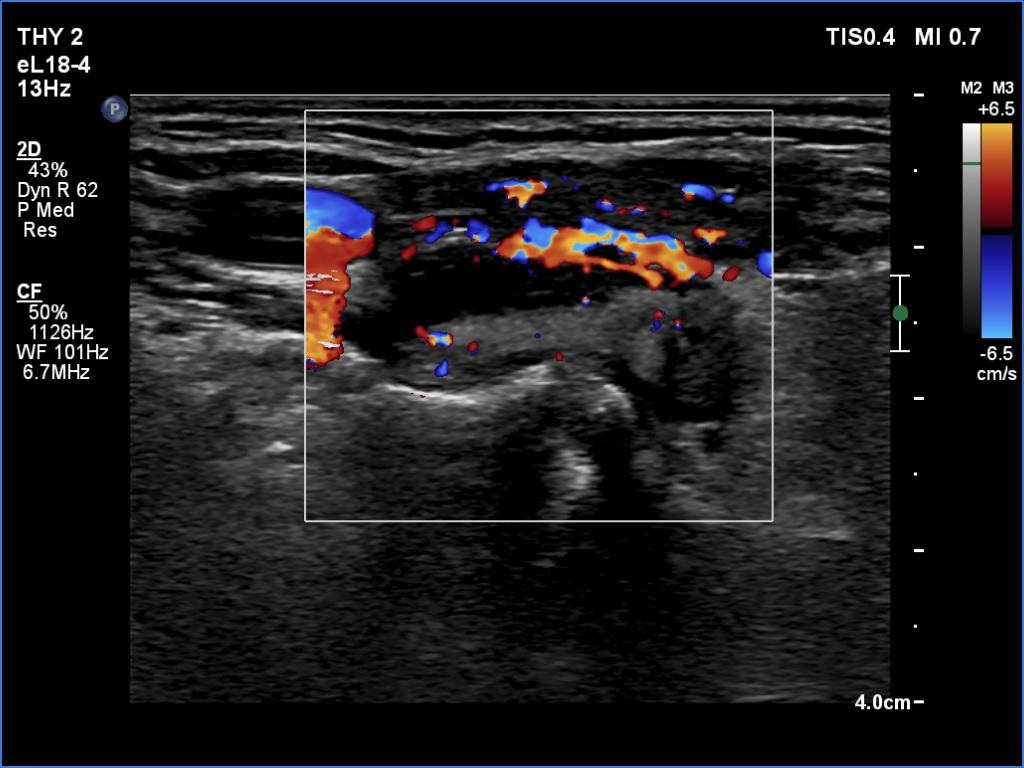

Parathyroid lesions - case 1521 (ultrasonographic picture 13)

Right lobe, transverse scan, color Doppler mode - after aspiration of 2 mL yellow fluid.